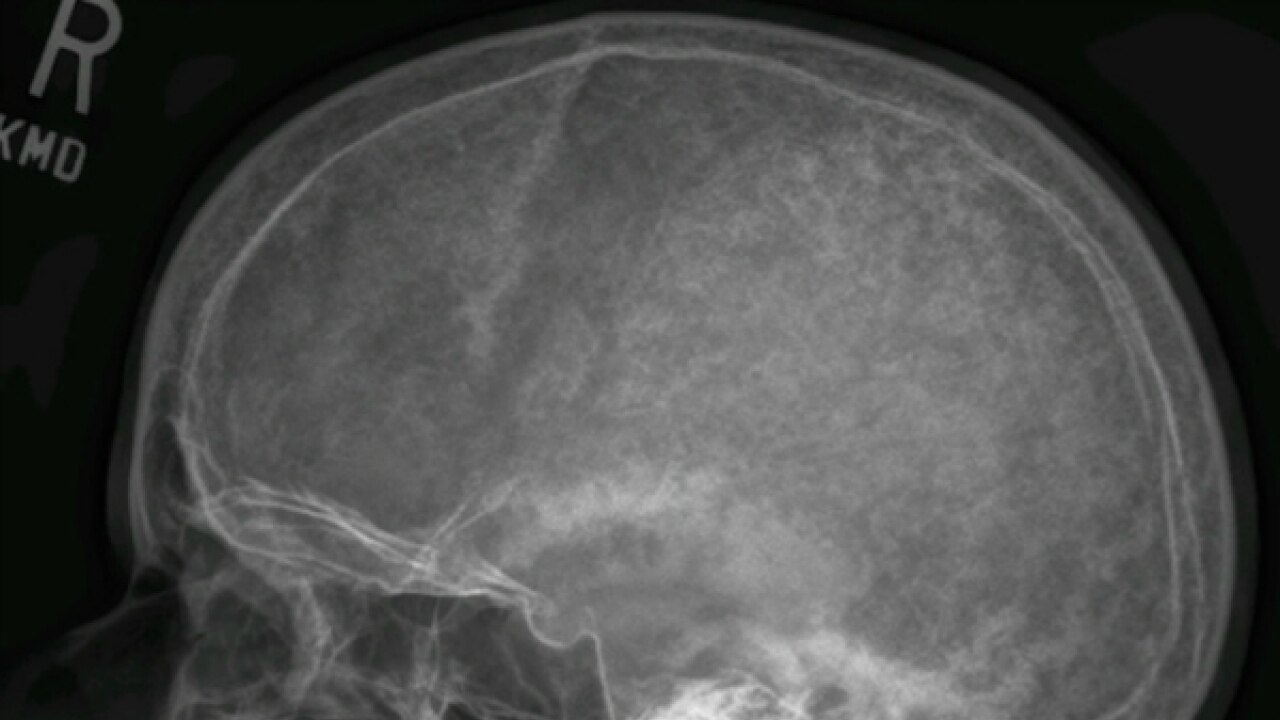

Cancer can affect the blood, altering normal blood.

How is bone cancer diagnosed? It also informs about the type of cancer. Bone cancer is a malignant (cancerous) tumor of the bone that destroys normal bone tissue. Bone pain, weight loss, swelling, and fractures are just some of the symptoms and signs of bone cancer. Watch the video explanation about rare bone cancer patient shares his story online, article, story, explanation, suggestion, youtube. What are bone marrow tests? A bone scan is an important diagnostic tool used to detect the presence of bone disorders such as osteoporosis or even bone cancer. How to prevent bone cancer. Bone cancer is a fairly rare disease, so if you've developed bone pain, don't jump to conclusions. The report provides information about the patient, the reason for the test, if contrast was given and what was found. Bone marrow tests are used to diagnose and monitor bone marrow diseases, blood disorders, and certain types of cancer. Here you may to know how to detect bone cancer. Find out how to prepare for and what to expect during a bone scan.

It is an imaging test that uses special gamma cameras and. This bone cancer detection tool may reveal whether the primary tumor has spread to other places in the bone, and how much damage it has caused. Imaging tests to detect bone cancer. Good and bad foods for psoriasis. Cancers that begin in the bone are called primary bone cancers. Secondary bone cancer occurs when cancers that develop elsewhere spread, or metastasize, to the bones. Bone marrow tests are used to diagnose and monitor bone marrow diseases, blood disorders, and certain types of cancer. This is a useful test for looking for cancer throughout a patient's body, and sometimes can help how many blood cells are present in your bloodstream.